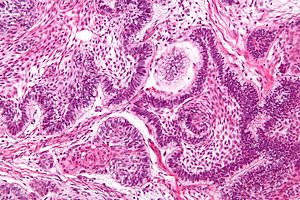

Ameloblastoma. H&E stain. | |

| LM | stellate reticulum (star-shaped cells), tall columnar cells that have palisaded nuclei with reverse polarization, subnuclear vacuolization, +/-giant cells, +/-subepithelial hyalinization (eosinophilic acellular amorphous material) |

Features:[7]

- Stellate reticulum - star-shaped cells, found in a developing tooth.

- Tall columnar cells.

- Palisaded nuclei with reverse polarization.

- Reverse polarization of nuclei = nuclei distant from the basement membrane/nuclei at pole opposite of basement membrane.

- Palisaded nuclei = picket fence appearance; columnar-shaped nuclei with long axis perpendicular to the basement membrane -- key feature.

- Subnuclear vacuolization.

- +/-Giant cells.

- +/-Subepithelial hyalinization (eosinophilic acellular amorphous material).

- Seen deep to the basement membrane.

- Variable morphology (see below - morphology).

- Follicular ameloblastoma (classic appearance).

- Plexiform ameloblastoma (does not have prominent palisading).